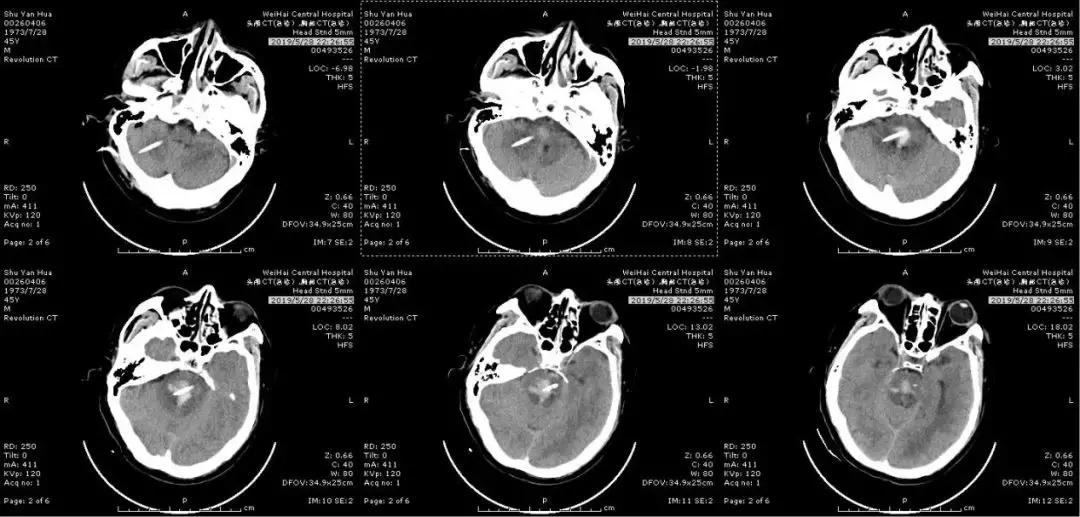

46岁的患者舒先生,5月24日上午突然头晕、呕吐,随即出现言语笨拙,四肢活动不灵,立即被送至威海市中心医院抢救。头颅CT检查示:脑干出血,出血量约3ml,期间患者持续内科保守治疗,但5月28日患者突然出现意识障碍加重、深度昏迷,呼吸急促、心率加快,复查头颅CT:脑干出血增多。出血量大于5ml,病情极其危重,已经危及生命。

(2019年5月28日入院后第4天血肿增多)